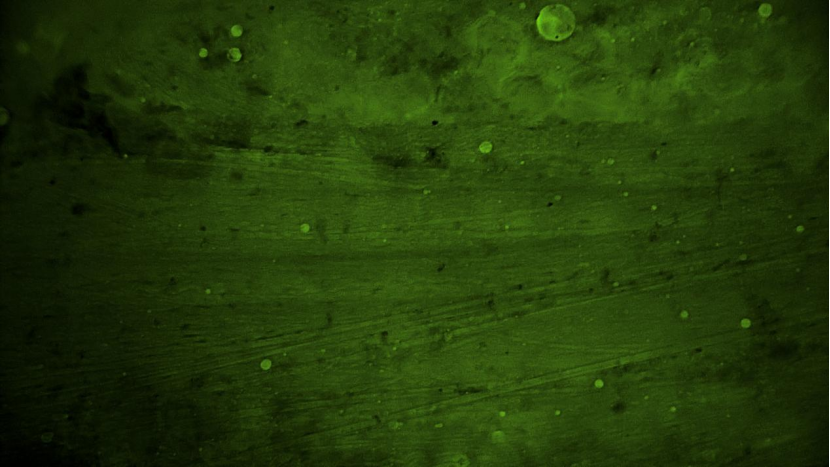

術中EndoSCell?細胞圖像如下:

血管組織:可見清晰血管及少量脂肪細胞,未見腫瘤細胞